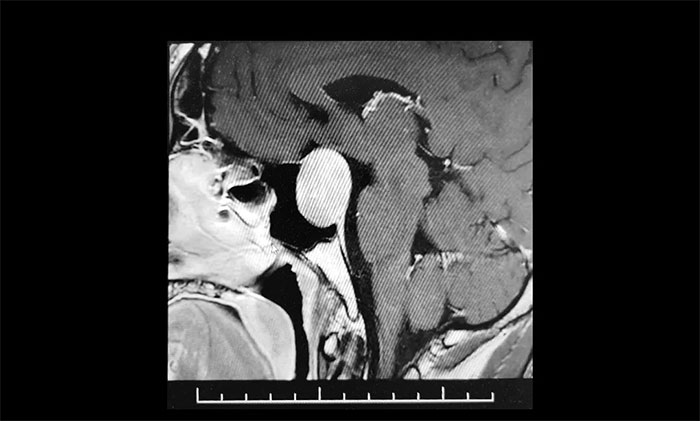

▲ 肿瘤侵袭生长,包绕左侧海绵窦

为求进一步确定病情,张先生在家人陪伴下,慕名来到上海蓝十字脑科医院。经鞍区MRI平扫+增强显示:蝶鞍显著扩大,鞍底下陷,垂体窝见类椭圆形异常信号,大小约3.1×2.7×2.1cm,病变向鞍上生长,推移视交叉上抬,与左侧海绵窦分界欠清晰,被包裹1/2。

神经外科6B病区专家李士其教授、潘仁龙主任、吴治群博士会诊后,考虑为侵袭性垂体巨腺瘤,乒乓球大小的瘤体压迫视神经,并且侵袭生长,左侧海绵窦部分受包绕,向上已突破鞍隔,压迫视神经、视交叉、下丘脑。如果肿瘤进一步生长,可能加重视力下降、甚至失明。